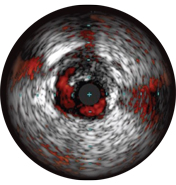

На мальаппозицию указывает наличие крови за стратами стента. При визуализации с использованием режима ChromaFlo кровоток окрашен в красный цвет для простого выявления мальаппозиции и других особенностей просвета.